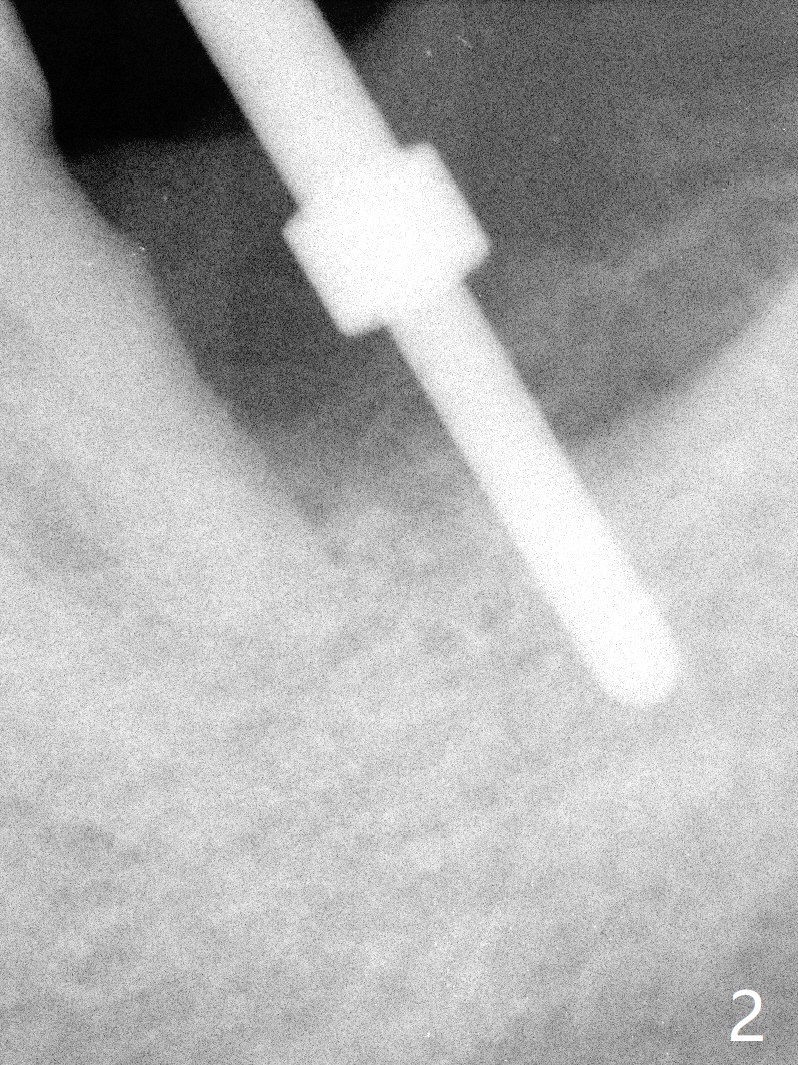

After extraction, curettage and Clindamycine gauzes in the sockets of the tooth #18 for 3 times, a 2 mm pilot drill makes initial osteotomy in the socket from 8 to 14 mm (Fig.1 (gingival level)). It appears that the osteotomy should move distal (Fig.1: red line, Fig.2 (17 mm)). After 5.9x10 mm drill, a 5.9 mm tap is placed (Fig.3). There is 4 mm clearance. Following 6.4x10 mm drill for 2 mm deeper, a 6.4x10 mm implant is placed with 60 Ncm. The implant plateau is level with the lingual crest, while the mesiobuccodistal bone is low. Autogenous bone mixed with Osteogen is placed in the defect area, followed by insertion of a 6.8x4(4) mm abutment (Fig.5). Collagen dressing is placed on the top of the graft. An immediate provisional is fabricated to close the remaining socket. Impression is taken 7 months postop (Fig.6). There seems to be no bone loss 23 months post cementation without opposing teeth (Fig.7) in spite of severe periodontitis at #19 (Fig.8 (25 months post cementation)). More surprising is the asymptomatic lingual (L) plate perforation, revealed by CT (Fig.9 arrowheads).